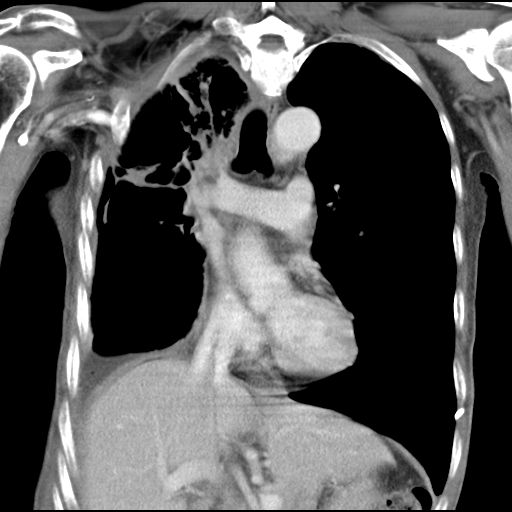

2020年5月12日,何叔来到复大就诊,检查结果:入院查CT示右肺中央型肺癌并右肺上叶及中叶阻塞性肺不张表现,肺腺癌T3bN2M1 Ⅳ期,伴胸膜、纵膈、右肺门等多发淋巴结转移,左侧胸腔中大量积液,右侧胸腔少量包裹性积液。针对何叔的病情,复大专家团队立马组织会诊,先后给予何叔静滴安维汀和两次动脉DSA+灌注化疗联合PD-1治疗,何叔的呼吸症状得到改善,肿瘤也从8.6公分缩小到4公分。

治疗后